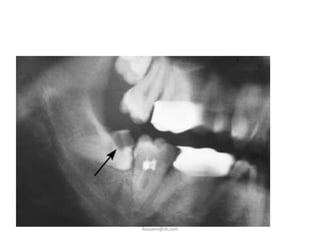

B. Dental Caries

• When third molar is

impacted or partially

impacted ,the bacteria

that cause dental caries

can be exposed to the

distal aspect of the 2nd

molar, as well as to

third molar